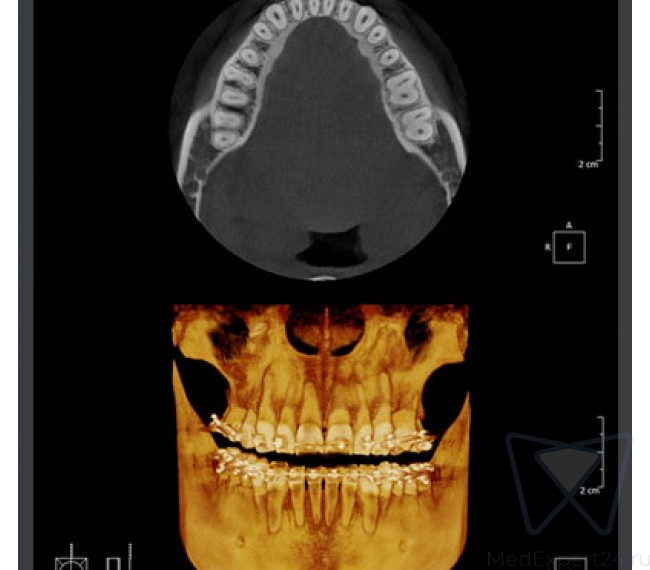

- Четкие изображения с помощью технологии MAR (Metal Artifact Reduction) – алгоритм уменьшения влияния артефактов, возникающих от металлов в челюсти. Уменьшает эффект отражения рентгеновских лучей от объектов с высокой плотностью и позволяет улучшить диагностику вокруг этих объектов.

Оптимальный размер области исследования (9x9 см) и разрешение 143 μm

Возможности компьютерного томографа:

- Изображения высокой четкости для эндодонтического лечения

- Высококачественная панорамная томограмма